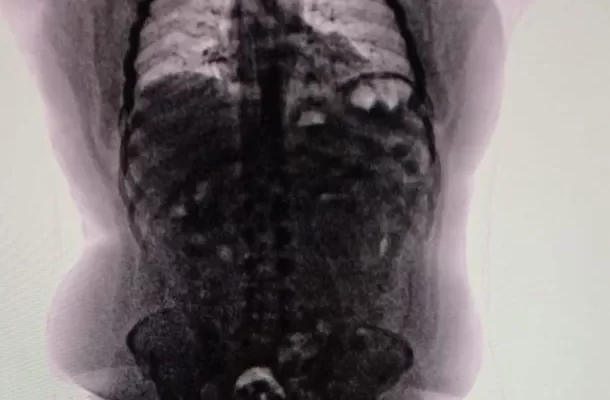

Tras un control con escáner corporal, se confirmó que transportaba múltiples cuerpos extraños en su interior. Fue inmediatamente internado en el Hospital de Ezeiza, donde permaneció bajo estricta vigilancia médica y policial durante cuatro días, período en el cual evacuó las 90 cápsulas que totalizaron 698 gramos de cocaína.